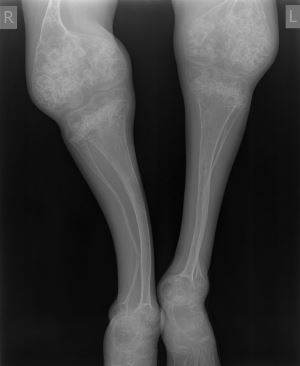

Рентген покажет разные результаты в зависимости от тяжести патологии. В любом случае будет заметен остеопороз, большое количество переломов разных по времени. Кортикальный слой костной ткани будет очень тонким кроме мест заживших переломов. Трубчатые кости будут искривлены. На их концах отмечают склероз ткани, которые появляется в процессе компенсации организма.

Характерно укорочение конечностей, из-за постоянных переломов трубчатых костей. Часто деформируются бедра и голени, иногда страдают предплечья и плечи. Могут образовывать ложные суставы.